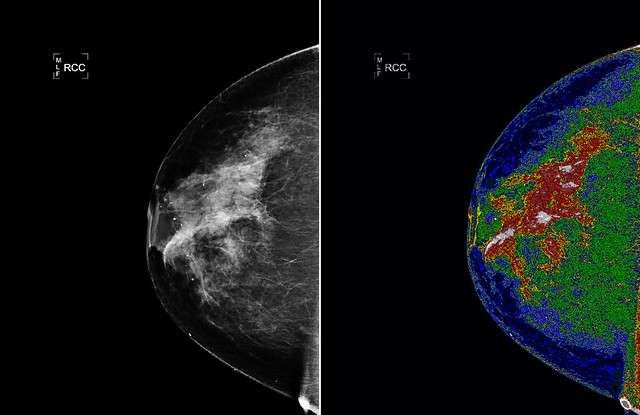

La bioimagen ha evolucionado desde la tecnología de rayos X hasta la de resonancia magnética (RM) y ultrasonidos. Sin embargo, nuevos estudios de investigación están utilizando tecnología de luz infrarroja cercana para desarrollar un sistema de bioimagen denominado tomografía óptica difusa (DOT). Esta forma de tecnología lumínica fue desarrollada originalmente por la NASA en su Laboratorio de Propulsión a Chorro para el uso de imágenes espectrales en misiones espaciales. A lo largo de la última década, los investigadores científicos han descubierto que esta misma tecnología puede aplicarse a la obtención de imágenes de los tejidos blandos del cuerpo humano. Tomografía e imágenes ópticas difusas (DOI) se basa en la tecnología de la luz en el espectro del infrarrojo cercano para medir las propiedades ópticas de los tejidos blandos del cuerpo.

Tejidos como el cerebral o el mamario son ideales para este sistema de imagen por sus propiedades translúcidas o de transmisión de la luz. Las variaciones en la transmisión y absorción de la luz pueden utilizarse para detectar los niveles de hemoglobina y oxígeno en la sangre, y estos datos pueden utilizarse después para crear una imagen espectral del tejido. Este proceso crea una imagen de alta resonancia que muestra claramente las anomalías y puede conducir a una detección y un tratamiento más tempranos en los pacientes. El análisis de los niveles de hemoglobina y oxígeno basado en la tecnología de la luz también se ha aplicado a otras áreas de tratamiento, como la medicina deportiva y la detección del desarrollo temprano del cerebro en fetos.

La instrumentación puede diseñarse específicamente para su uso en el campo médico y en ámbitos específicos de la bioimagen como el DOT. La tecnología de infrarrojo cercano puede medir y cuantificar datos utilizando las variaciones en los niveles de oxígeno de la hemoglobina para crear un intrincado mapa espacial de los tejidos transmisores de luz. Esta nueva tecnología cambia continuamente a medida que surgen nuevos avances en la tecnología de la luz. El futuro de nuestro sistema sanitario depende de avances tecnológicos como éste para aumentar la detección precoz de células anormales en los tejidos y alertar a los pacientes de la necesidad de un tratamiento adicional. Lo ideal es que este nuevo sistema de bioimagen basado en la tecnología de la luz permita una detección más precoz y tratamientos que salven vidas.